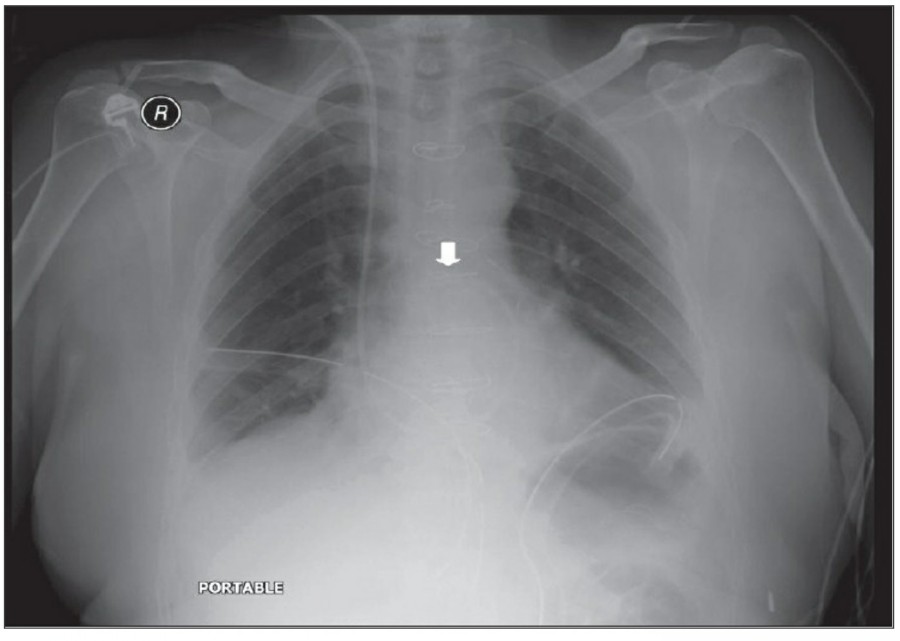

중환자에서 pneumothorax의 진단은 종종 supine radiograph에서 내릴 수 있다. Supine position에서 공기는 anteromedial 방향으로 모이게 되는데, apical air collection이 있을 경우 large pneumothorax가 있음을 시사한다. 공기는 lung과 diaphragm 사이의 subpulmonic location에 trap 되어 있을 수도 있다. 공기가 costophrenic sulcus로 anterolateral extension 될 경우, 이 costophrenic sulcus의 radiolucency를 증가시키는데, 이를 deep sulcus sign이라고 한다. Subpulmonic pneumothorax의 다른 특징으로 diaphragm의 superior surface와 IVC 윗부분이 뚜렷하게 보일 수 있다.

중환자에서 tension pneumothorax의 진단은 매우 힘들다. ARDS와 같은 lung의 병리적인 기전이 lung compliance를 감소시킴으로써 total lumg collapse를 막는다. 또한 tension pneumothorax의 특징인 mediastinal shift가 PEEP으로 인해 나타나지 않을 수 있다. Chest X ray 상에서 tension pneumothorax는 hemidiaphragm의 depression이나 heart border, SVC, IVC의 이동으로 나타날 수 있다.